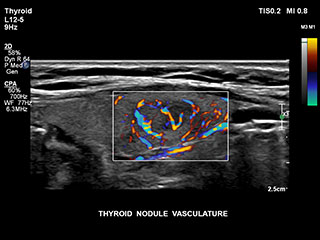

Bisher war die Erfassung von Flussdaten bei kleinen Gefässstrukturen mit niedriger Flussrate schwierig. Die neue EPIQ Funktion MicroCPA bietet eine schnelle und einfache Darstellung von Mikrozirkulation mit niedriger Geschwindigkeit und ermöglicht eine hohe Diagnosesicherheit bei der Beurteilung der Organperfusion oder von kleinen Gefässbetten.